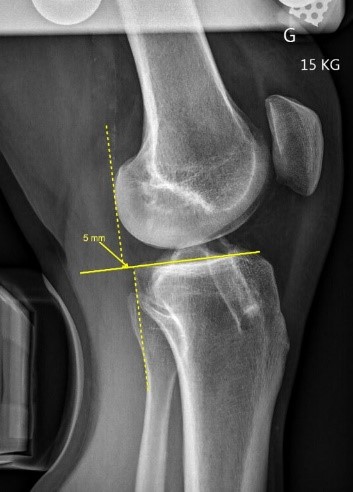

Le Telos Stress est un appareil permettant de réaliser les examens en salle de radiologie visant à tester la stabilité et quantifier la laxité des ligaments des  articulations.

Cet Appareil est particulièrement adapté à l’étude fonctionnelle des ligaments croisés des genoux LCA et LCP et ligaments collatéraux des chevilles avant toutes décisions thérapeutique ou chirurgicale.

La méthode est précise et reproductible car le positionnement est toujours identique et la force exercée est étalonnée.

Les mesures réalisées sur les images radiographiques permettent d’obtenir un diagnostic précis pour le prescripteur.